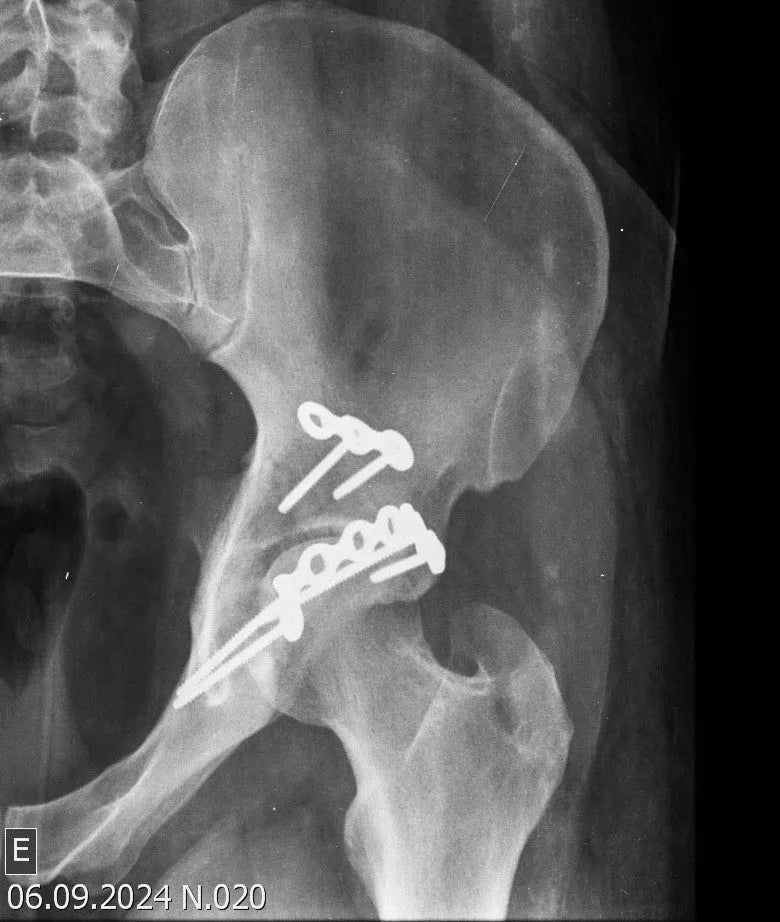

- Identificação e Redução Precisa dos Fragmentos: Saiba como identificar os fragmentos inferior e superior do teto acetabular. Aprenda a limpar e descolar a articulação para melhor identificação dos parâmetros de redução, e reposicionar os fragmentos em seus locais anatômicos após a redução da luxação.

- Fixação Definitiva com Múltiplas Placas: Aprenda a fixar a placa principal no ísquio, contornando todo o rebordo posterior, com parafusos direcionados para o teto acetabular. Utilize uma segunda placa no vértice do fragmento superior para fixação. Compreenda como a utilização dessas duas placas proporciona redução e estabilidade satisfatórias, eliminando a necessidade de placas em mola.

- Reconstrução Anatômica e Fechamento: Realize a identificação e reconstrução dos tendões piriforme, gêmeo superior, gêmeo inferior e obturador interno. Aprenda a reinserir o piriforme em sua posição original, com discreta rotação externa do quadril auxiliando na reinserção dos tendões. Restaure a estrutura anatômica com preservação do quadrado femoral e do glúteo médio, sem cortes musculares. Finalize com a sutura do trato iliotibial.